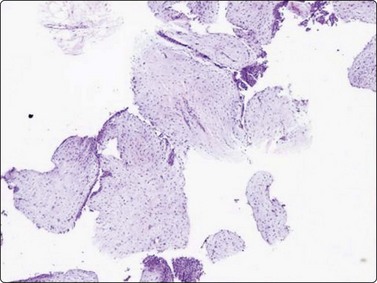

image image

Fig. 7.15 Regenerative epithelial atypia in mastitis

(A) Atypical, reactive/regenerating epithelial cells with a background of histiocytes, inflammatory cells and debris (MGG, HP); (B) Corresponding tissue section (H&E, IP).